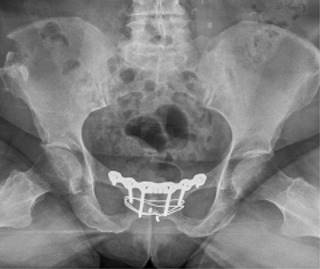

Se seleccionaron dos pacientes de 65 y 72 años. Ambas presentaron dolor en la sínfisis que les limitaba las actividades de la vida diaria. Una de ellas realizaba actividad física moderada que había tenido que cesar por completo debido a las molestias continuas. Se realizaron estudios de imagen que comenzaron con radiografías simples de pelvis (Figura 3).

Figuras 3: Radiografía flamenco y anteroposterior. Imágenes correspondientes a las pacientes de nuestra serie. En ambas se pueden apreciar cambios degenerativos que afectan al hueso subcondral con irregularidad y disminución del espacio de la interlínea articular.

Ambas pacientes fueron mantenidas en descarga durante cuatro semanas, con autorización para carga parcial a partir de la cuarta. Se sometieron a revisiones ambulatorias trisemanales, durante las cuales se observó una reducción escalonada de la analgesia y un aumento en la autonomía para las actividades diarias. En las revisiones, se realizaron radiografías en proyección anteroposterior y en carga (Figuras 8 y 9). A las 12 semanas, iniciaron ejercicios moderados sin impacto. El dolor significativo en la sínfisis del pubis, que inicialmente impedía la deambulación, se redujo gradualmente hasta su completa desaparición, con puntuaciones de 1 en la EVA. No se requirió la retirada del material de osteosíntesis en ninguna de las pacientes durante el seguimiento hasta el momento actual tras dos años de seguimiento.

Figura 8: Radiografía anteroposterior de control postquirúrgico a seis semanas de una de las pacientes. Fusión incipiente de sínfisis.